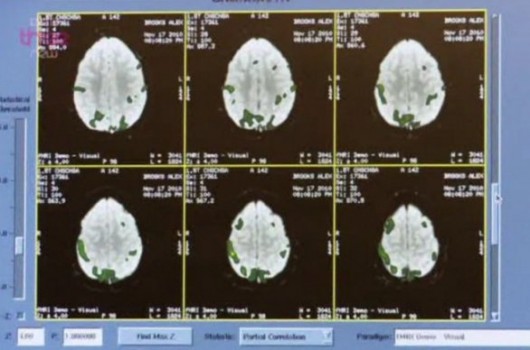

Il conduttore del programma, Alex Riley, ha deciso di contattare il redattore di World of Apple, Alex Brooks, un fanatico dell’azienda di Cupertino che dichiara di pensare alla compagnia “24 ore al giorno”. Una squadra di neuroscienziati ha quindi studiato il cervello di Brooks tramite una risonanza magnetica, osservando le reazioni alle immagini di prodotti Apple e di prodotti di compagnie concorrenti.

In seguito a varie analisi i neuroscienziati hanno dichiarato che:

i prodotti Apple innescano bit identici del cervello di Brook rispetto a quelli innescati da immagini religiose nei fedeli. Ciò suggerisce che i grandi brand della tecnologia hanno sfruttato o aperto le aree cerebrali che si sono evolute per elaborare la religion.